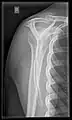

X-ray

Projectional radiography views of the shoulder include:

- AP-projection 40° posterior oblique after Grashey

The body has to be rotated about 30 to 45 degrees towards the shoulder to be imaged, and the standing or sitting patient lets the arm hang. This method reveals the joint gap and the vertical alignment towards the socket.[26]

- Transaxillary projection

The arm should be abducted 80 to 100 degrees. This method reveals:[26]

- The horizontal alignment of the humerus head in respect to the socket and the lateral clavicle in respect to the acromion

- Lesions of the anterior and posterior socket border, or of the tuberculum minus

- The eventual non-closure of the acromial apophysis

- The coraco-humeral interval

CR. shoulay film.

Transaxillary conventional radiography